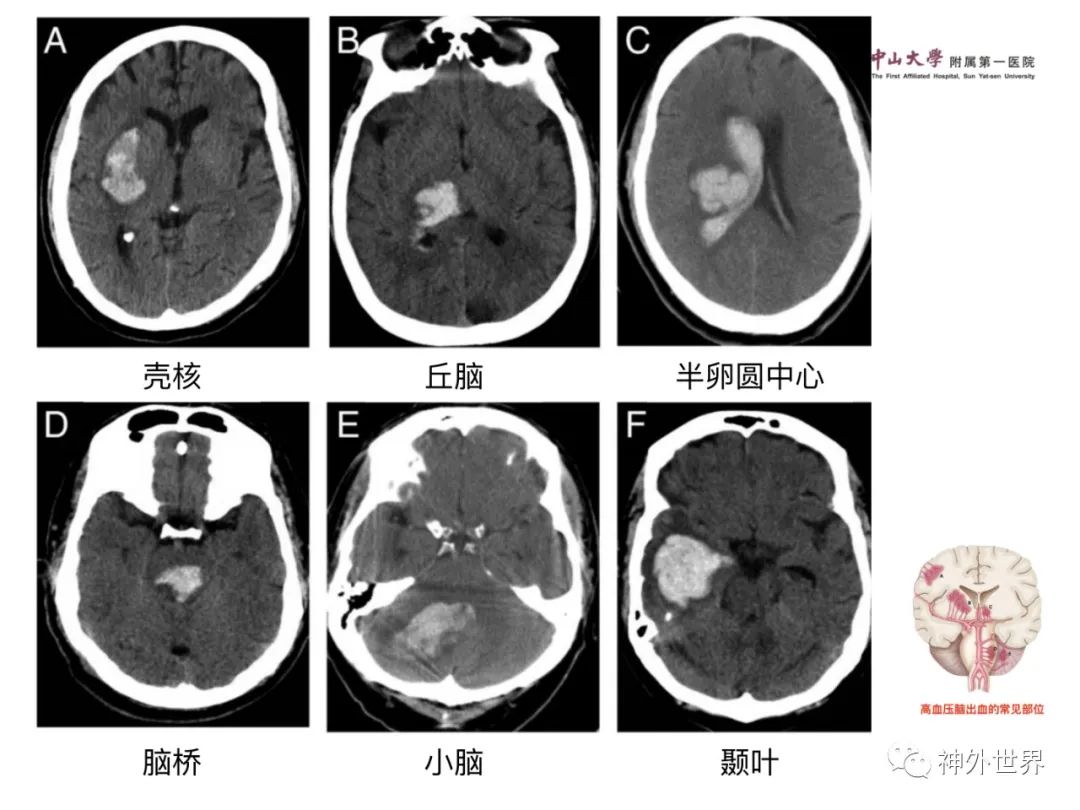

大脑MR、CT 的阅片技巧,超赞 !